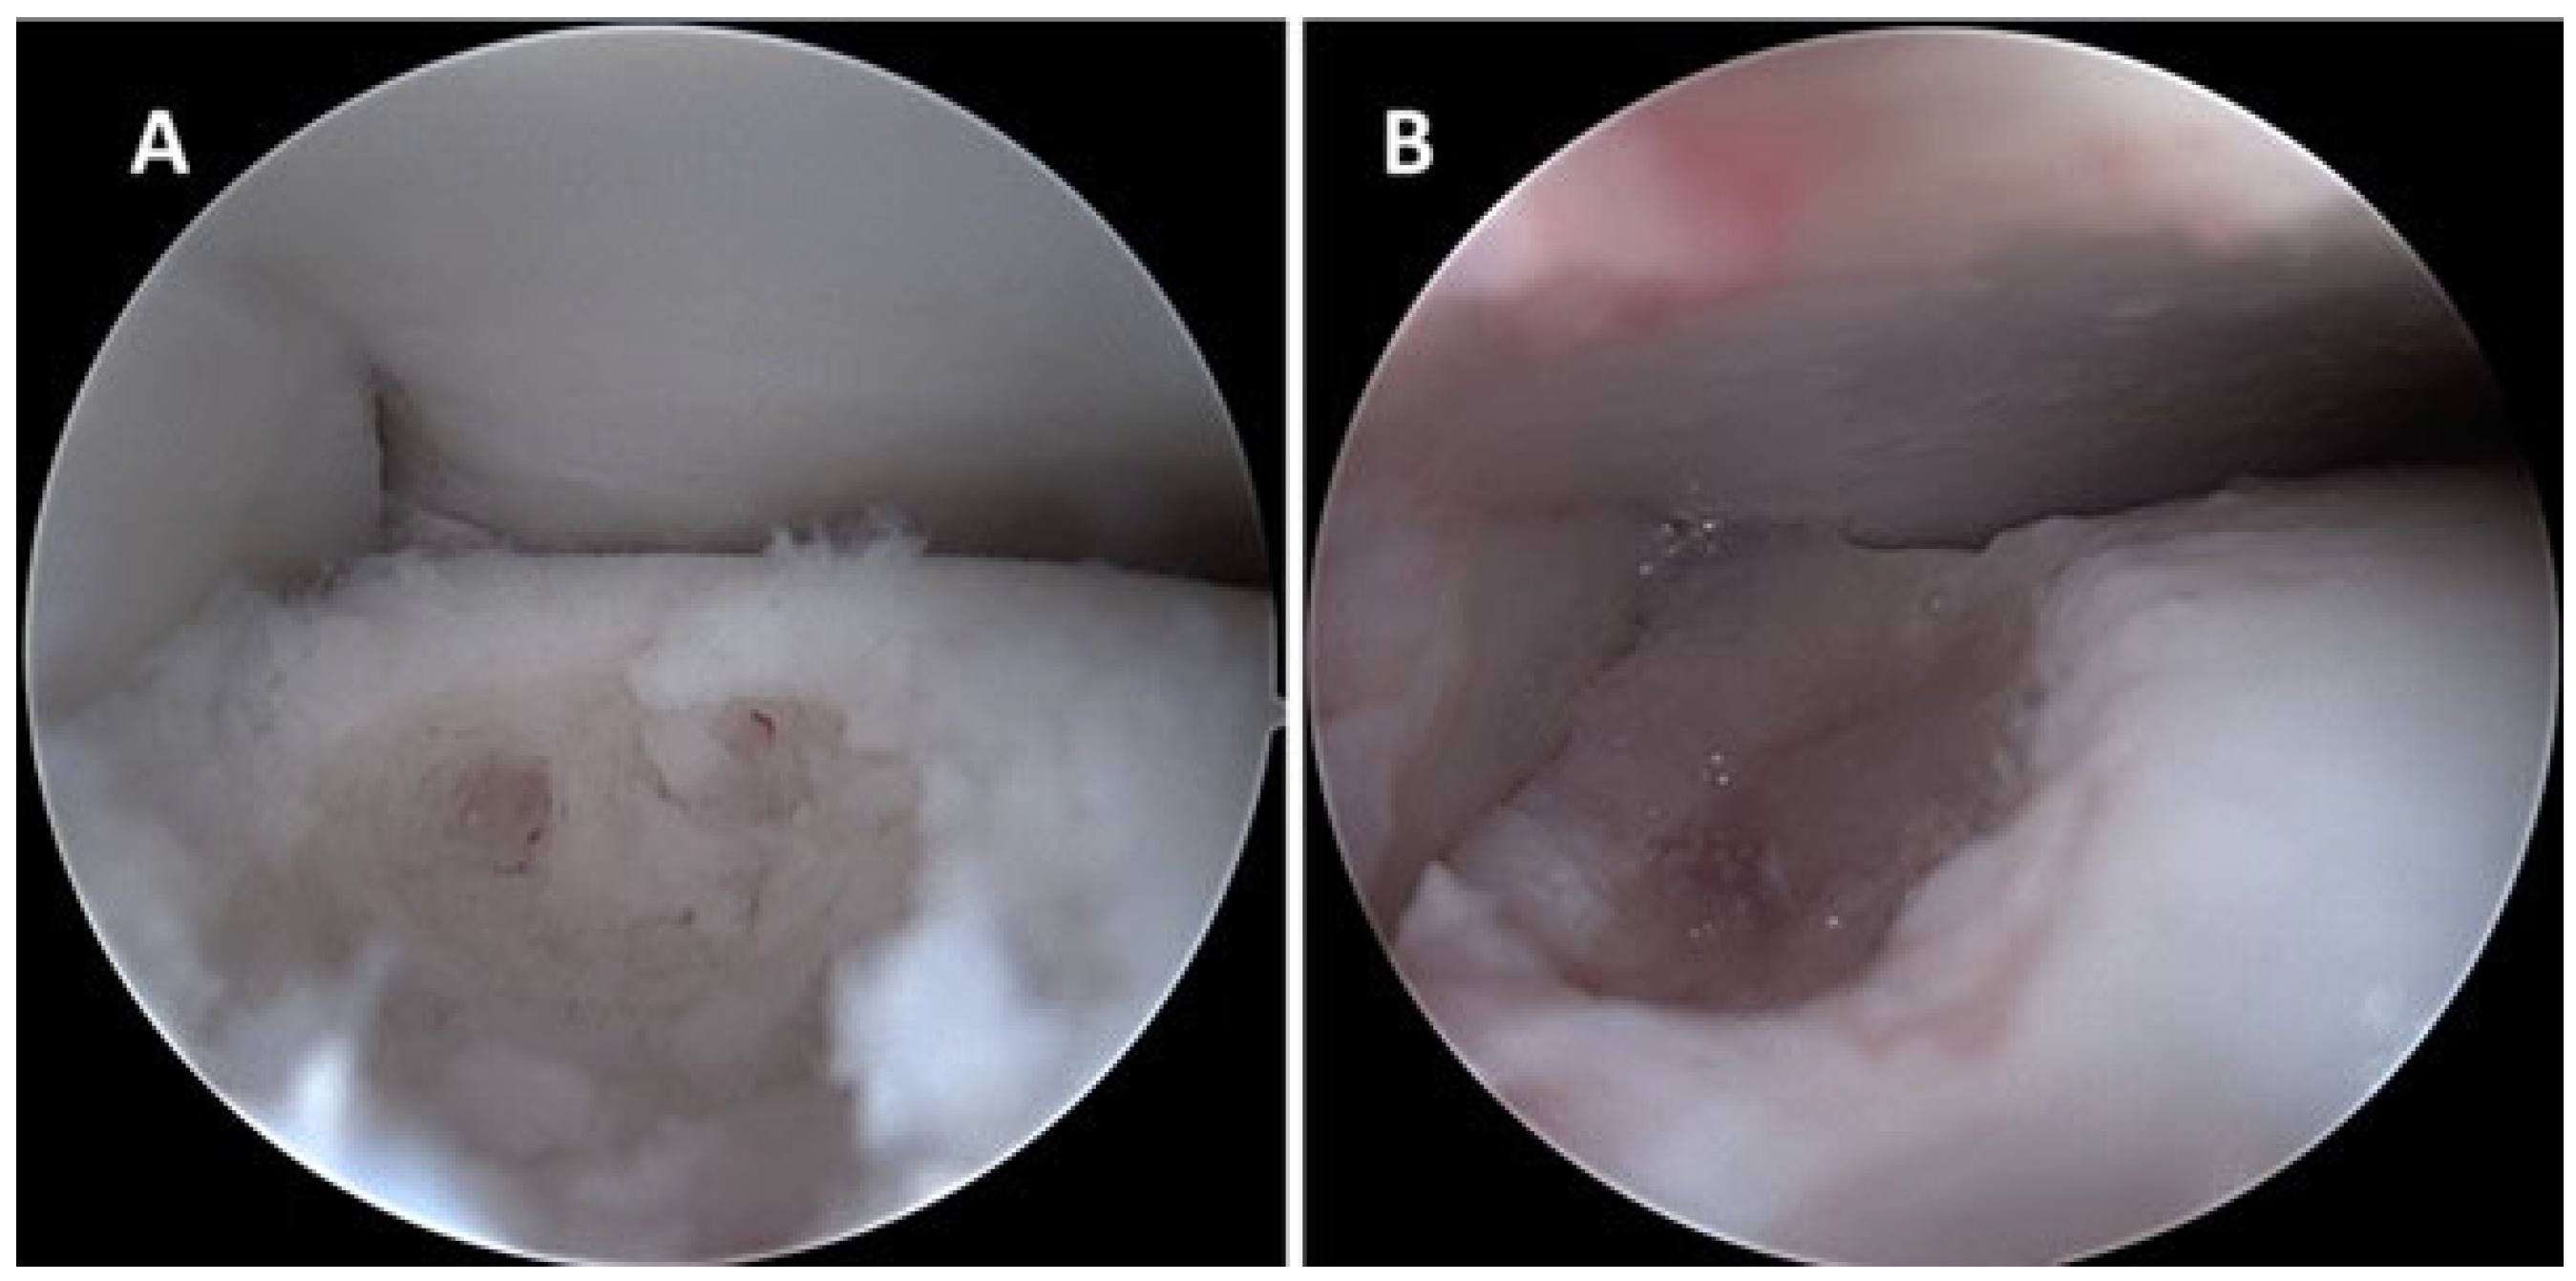

2. Case Presentation